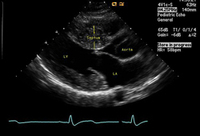

Hypertrophic cardiomyopathy

Long axis echocardiography view - asymmetrical septal hypertrophy

From the collection of Dr Anji T. Yetman MD, University of Utah; used with permission